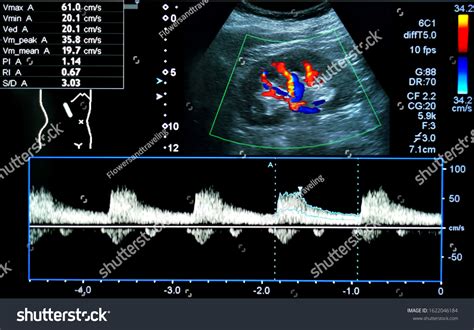

Detection usually occurs during the second or third-trimester anatomy scan. Sonographers look for a fluid-filled, cyst-like structure within the fetal abdomen that shows blood flow when color Doppler ultrasound is applied. Because the structure is vascular, it is easily distinguishable from other fluid-filled cysts (like those in the gallbladder or bowel) once the appropriate imaging techniques are utilized.

• Doppler Flow Studies: These studies measure the velocity and pattern of blood flow through the varix to check for turbulence or restricted flow.

Detection Method Color Doppler Ultrasonography